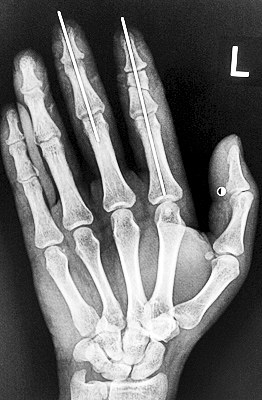

術后X光顯示,骨骼對位良好。

最終,盧微波和團隊找好了需要的血管和神經(jīng),做好標記后,開始固定食指骨骼、吻合肌腱,最后在顯微鏡下用直徑20微米的無創(chuàng)顯微縫合線開始吻合血管和神經(jīng)。

在經(jīng)過兩個多小時手術后,早上8時許,盧微波下令松止血帶,數(shù)十秒后男子蒼白的食指逐漸紅潤起來,食指在離體10個小時后恢復血運。

緊接著,盧微波又開始中指再植手術。上午10時許,中指在離體12小時后也成功恢復血運。